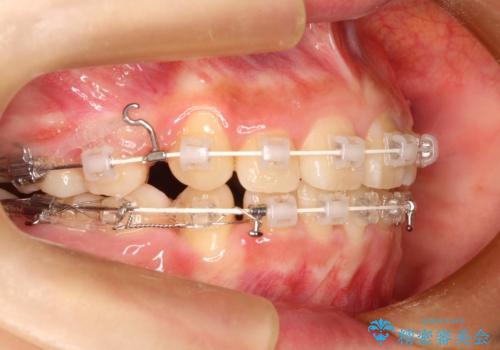

20代女性 非抜歯をオーソドックスなワイヤー矯正で

- 審美装置

- 10ヶ月

- 非抜歯or 抜歯にて悩まれましたが、非抜歯にて早めに終了することで合意

→ワイヤーにて治療をすすめることとなった